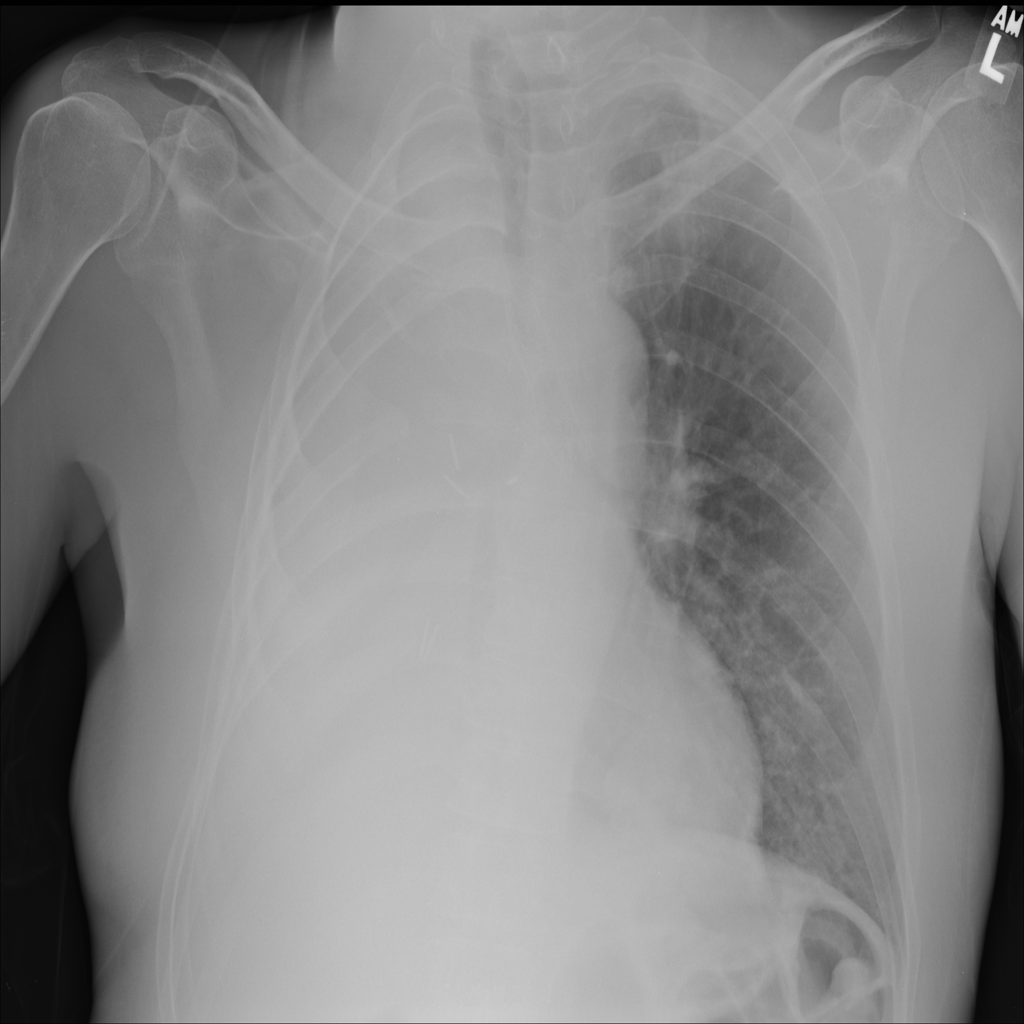

Consolidation

Consolidation refers to air-space filling that makes part of the lung appear denser on imaging.

Showing up to 90 reference images for Consolidation.

PAT-531A · IMG-006Consolidation

PAT-531A · IMG-006

PA